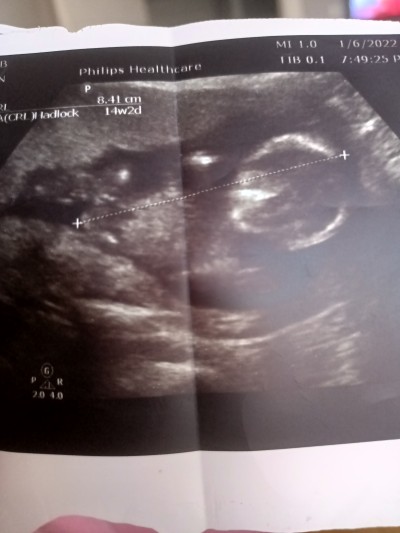

Merhaba anneler cinsiyet tahmini yapabilecek olan varmı acaba doktor net birşey söylemedi şimdiden teşekkürler

Gebelik haftası 15+5